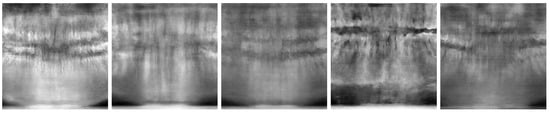

Figure 6 and Figure 7 show the best and worst generated images, respectively, as determined by the average scores for all twelve criteria. The best images show a reasonable depiction of both the overall morphology and certain details, although not at the level of contemporary real-world panoramic radiographs. The worst images display various issues, including poor overall image quality and manifestations of extra rows of tooth crowns.

Figure 7. Worst images among all model variants, showing poor overall anatomical depiction and severe artifacts.